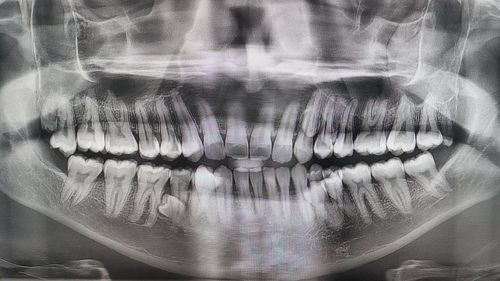

Prathab Muniandy dari Malaysia secara rasmi memegang rekod dunia bagi jumlah gigi terbanyak dalam mulut seorang lelaki, dengan jumlah keseluruhan 42 batang gigi iaitu 10 batang lebih banyak daripada jumlah gigi manusia biasa.

Untuk pengetahuan, kebanyakan orang dewasa hanya mempunyai 32 batang gigi, termasuk gigi geraham bongsu. Namun bagi Prathab, keadaan unik pada rahangnya menyebabkan beliau mempunyai 42 batang gigi yang tumbuh secara semula jadi.

Keadaan ini dikenali dalam dunia perubatan sebagai hyperdontia, iaitu situasi di mana seseorang mempunyai gigi tambahan melebihi jumlah normal.

Menurut laporan, doktor yang memeriksa mulut Prathab pada awalnya turut terkejut dengan jumlah gigi yang luar biasa tersebut. Selepas pemeriksaan dan pengiraan dibuat, jumlahnya disahkan mencecah 42 batang gigi menjadikannya pemegang rekod dunia bagi kategori lelaki.

Kes seperti ini sangat jarang berlaku. Hyperdontia biasanya hanya melibatkan satu atau dua gigi tambahan, tetapi mempunyai 10 batang gigi ekstra seperti Prathab memang luar biasa.